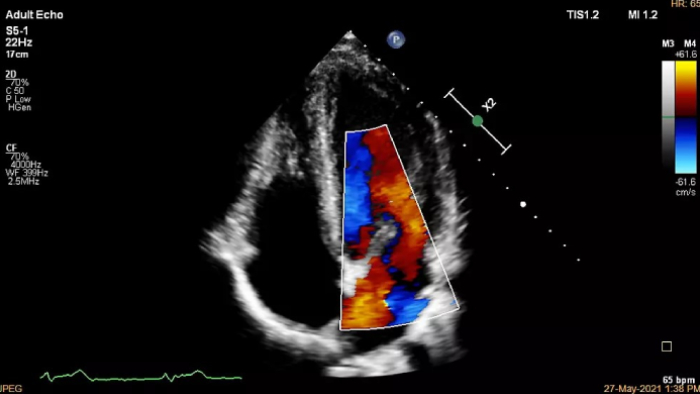

Increase diagnosis confidence and clinical efficiency through superior image quality, advanced quantification tool and automation technology.

If you were registered for ESC 2023, but were not able to attend the satellite symposium, you can still view it through the ESC website. Top cardiology thought leaders addressed some of the major challenges in peri-interventional and diagnostic echocardiography, such as advancing and complementing imaging techniques during tricuspid valve interventions, a revolutionary imaging workflow for occlusion of the left atrial appendage, and the importance of first-time-right ultrasound imaging during cancer therapy.